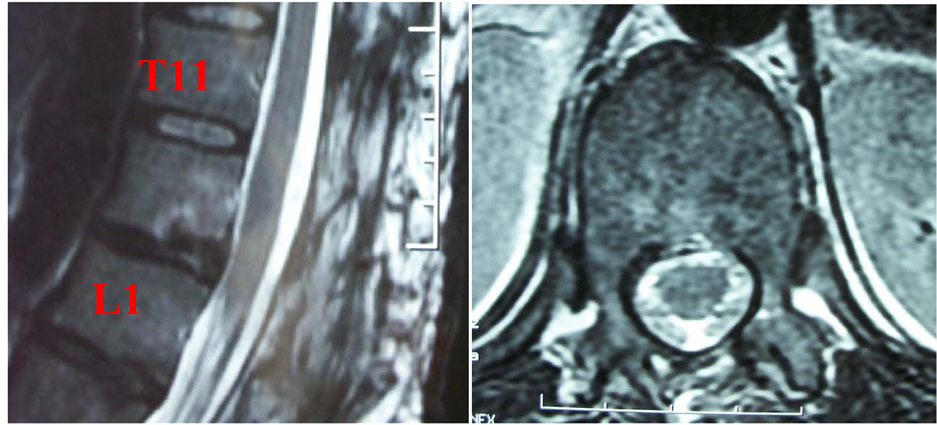

A postoperative MRI study (Figure 2) showed a total evacuation of the epidural hematoma and continues to feel well since ten months.

Figure 2. Postoperative T2 weighted MRI shows a complete decompression of the spinal cord (a) (b).